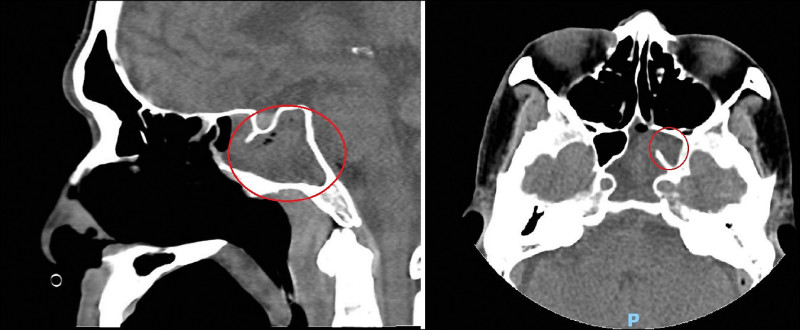

55歲的李姓男子大約半年前出現頭痛症狀,偶爾會劇痛,之後又出現複視、吞嚥障礙、手腳無力,日前因頭痛劇烈急診,並住進加護病房。經跨科檢查發現,他是鼻竇最深處的左側蝶竇發炎膿腫,壓迫腦神經產生各種症狀,臨床上相當罕見,經內視鏡清除病菌後慢慢復原。

加護病房主任林文培說,原本以為李男是腦膜炎,經檢查後予以排除,再經電腦斷層及核磁共振攝影,發現其鼻腔最深處的左側蝶竇不正常顯影,疑似佈滿膿瘍,壓迫到第3至第6對腦神經,才出現頭痛、複視等各種症狀。

許嘉方說,鼻竇位於鼻腔、眼窩及顱底頭骨內的顏面骨中的空腔,共有4對,包括上頜竇、篩竇、額竇及蝶竇,而蝶竇位在鼻孔內的最深處,恰在頭顱的正中央,緊鄰顱腦的重要神經,一旦發炎腫脹可能導致災難性的併發症。